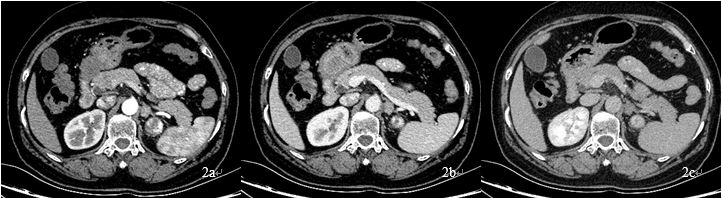

病例资料 患者女性,58岁,既往体健,查体发现左肾占位,行泌尿系CTU扫描,左肾占位呈典型 “快进快出”强化方式(图1),考虑肾癌、透明细胞癌可能性大。左肾上腺见结节灶,呈明显均匀强化(图2),肾上腺转移瘤待排,行能谱CT检查。

图2:左肾上腺见一结节灶,三期强化CT值分别为63Hu、82Hu、91Hu,呈渐进性强化,转移瘤?原发肿瘤?